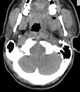

Neck infection